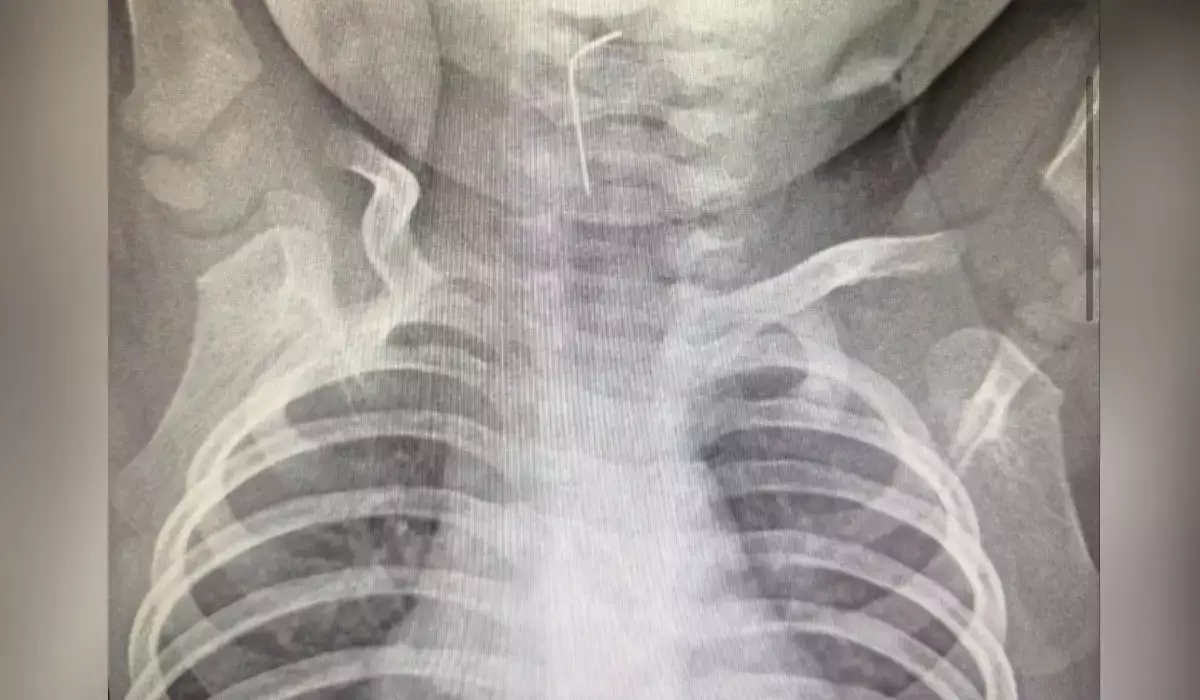

Түркістан облысында тоғыз айлық сәби ине жұтып қойған